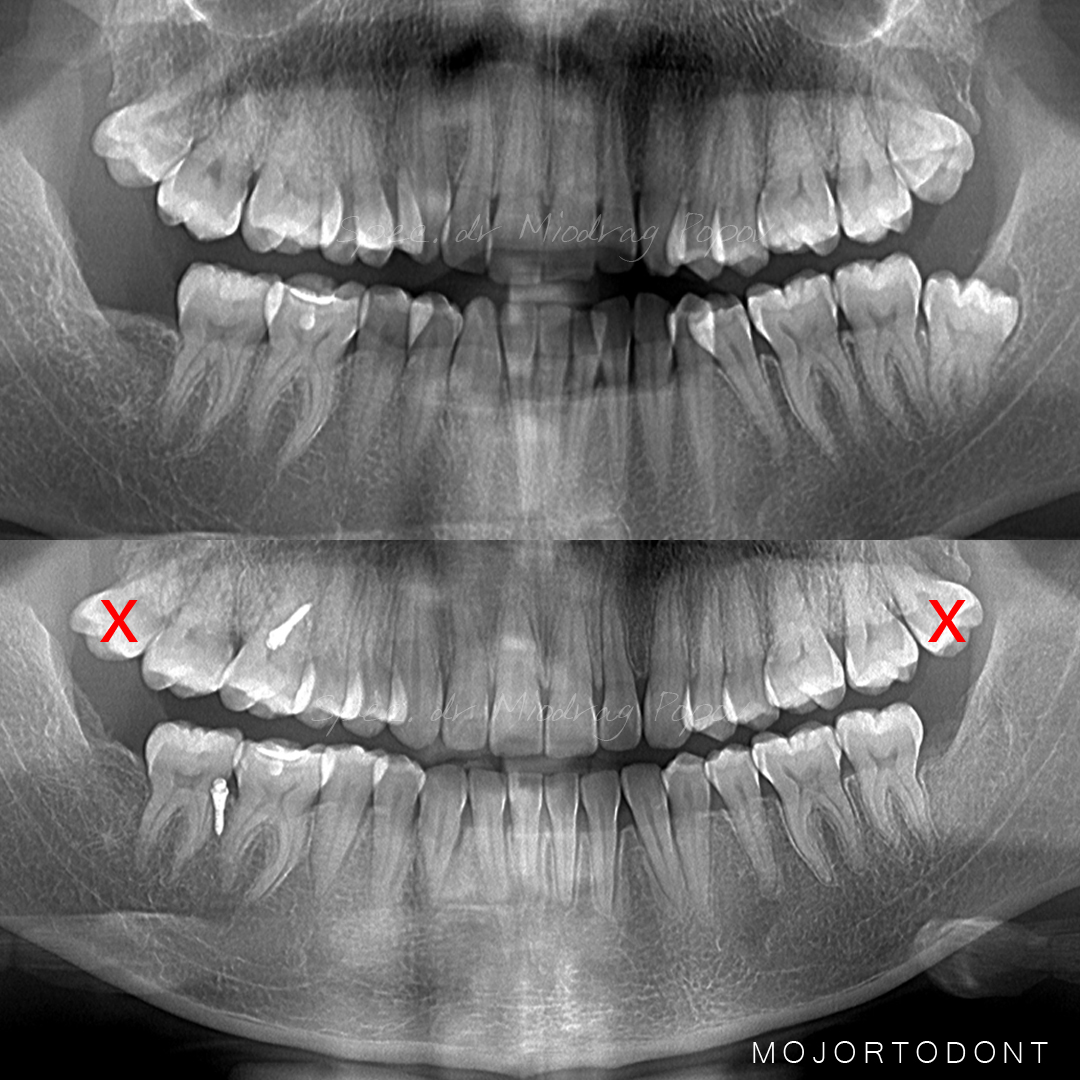

Jedan od naših top slučajeva iz 2024. godine!

Uz pomoć mini implantata uspeli smo da rešimo sledeće nepravilnosti kod pacijenta:

- 1/2 III klasa obrnutim prekolopom gornjih frontalnih zuba

- Teskoba u gornjem i donjem zubnom nizu

- Neusaglašene sredine zubnih nizova

- Jednostrano ukršten zagrižaj

Preciznost i stabilnost koje pružaju mini implanti omogućile su nam vrhunski rezultat!